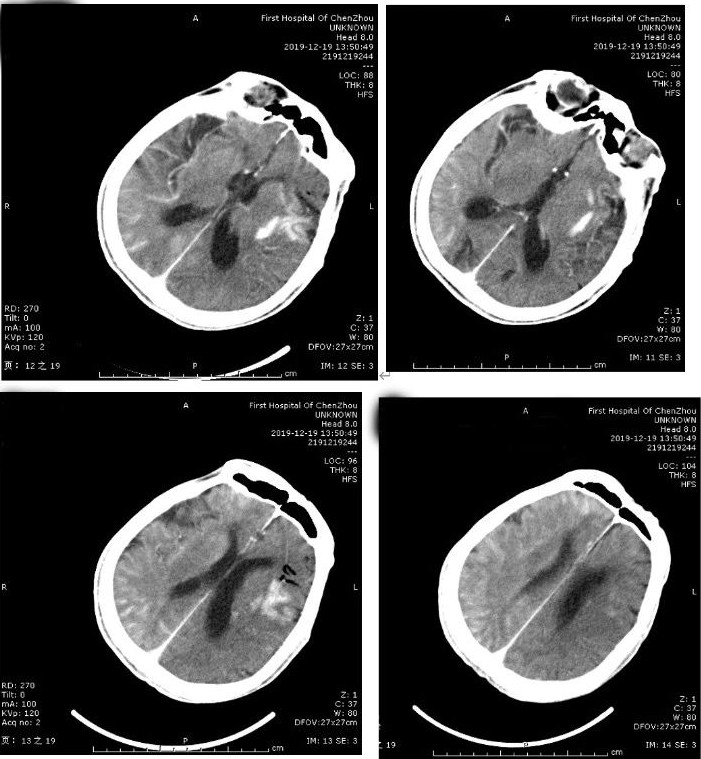

急诊头颅CT:左侧大脑中动脉高密度征,

ASPECT评分:9分。